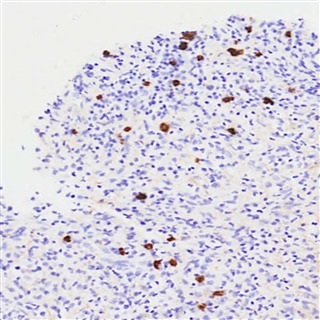

|

| IgG4陽性形質細胞の増加 | IgG4+ 形質細胞の上昇 (ほとんどの臓器で >10 細胞/HPF、膵臓と腎臓 >50 細胞/HPF) は診断をサポートしますが、単独では十分ではありません。この場合、IgG4陽性形質細胞はIgG陽性形質細胞集団全体の>40%を占めており、これはIgG4関連疾患の2019 ACR/EULAR分類における主要な診断基準となります。 (IgG4免疫染色、×400) |